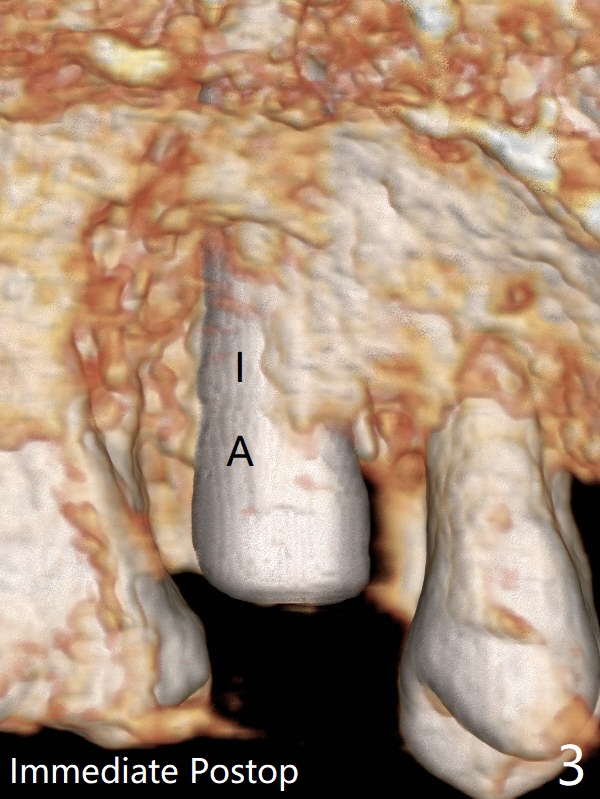

When a 4x11 mm FC is placed to the depth at #13, the palatal crestal bone is indistinct on probing. The implant is then placed ~ 1 mm deeper. To avoid contact between the future abutments and the mesiobucco-distal crest, a 5.5 mm profile drill is used. It appears that a 5x4 mm healing abutment has clearance from the crest (Fig.1,2 C). Immediate postop CT 3 D palatal view shows slight possible implant (Fig.3 I) thread exposure disto-palatal. To avoid this situation, the implant should have been designed more buccal (Fig.4 coronal section) because of the preexisting palatal defect (Fig.5,6) with low bone density palatocoronally (Fig.7). CT should have been taken prior to extraction. PRF or GEM21S should have been used. The patient will return for restoration (probably progressive loading) 3 months postop. In fact a pair abutment is placed 6 months postop (due to coronavirus, Fig.8). There is crestal bone palatal to the implant 6.5 months postop (Fig.9).